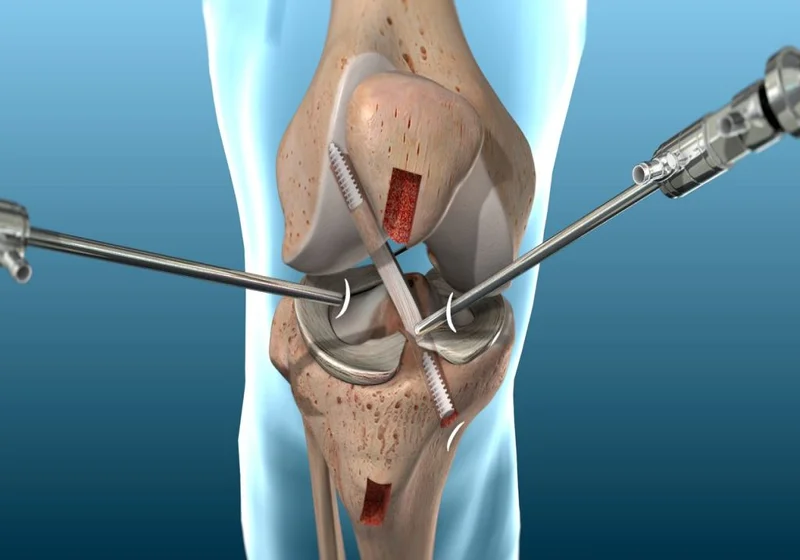

A cirurgia minimamente invasiva oferece uma alternativa promissora para o tratamento de condições no joelho e quadril, com benefícios significativos para os pacientes.

1. Menor trauma cirúrgico:

As técnicas minimamente invasivas geralmente utilizam incisões menores, o que resulta em menos trauma para os tecidos circundantes. Isso pode ajudar a reduzir a dor pós-operatória e acelerar a recuperação.

2. Recuperação mais rápida:

Pacientes que se submetem a cirurgias minimamente invasivas tendem a ter um tempo de recuperação mais curto. A diminuição do trauma cirúrgico facilita o retorno às atividades diárias e esportivas.

3. Menor risco de complicações:

Com menos invasão nos tecidos, há uma redução no risco de complicações como infecções e hemorragias. Isso resulta em um período de internação hospitalar mais curto e uma recuperação mais segura.

4. Menores cicatrizes:

As incisões menores resultam em cicatrizes menos visíveis, o que pode ser um fator importante para muitos pacientes que se preocupam com a estética após a cirurgia.

5. Menos dor pós-operatória:

Graças ao menor trauma e à abordagem menos invasiva, muitos pacientes relatam menos dor após a cirurgia, permitindo um controle mais fácil da dor com medicamentos simples.